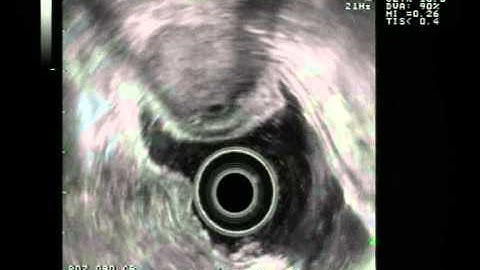

Stomach malignant GIST